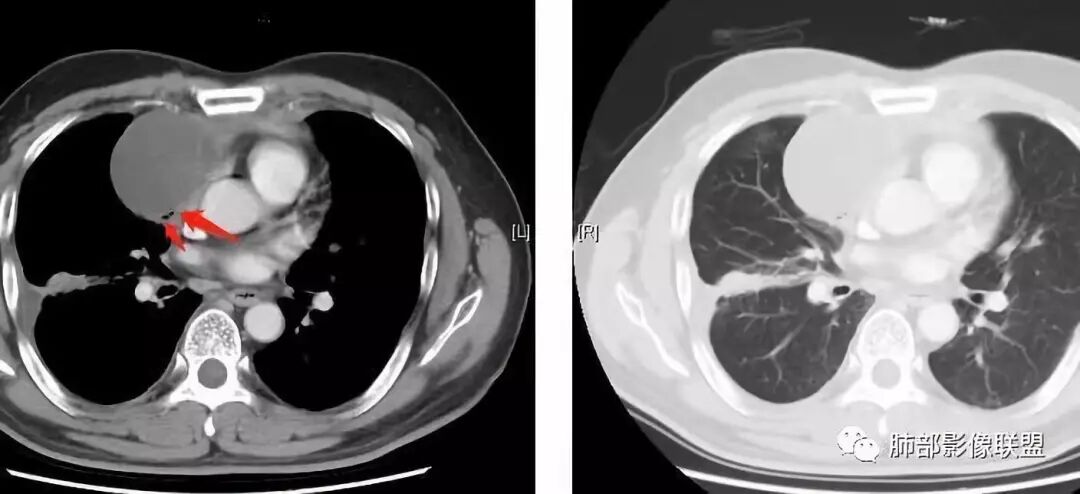

大家仔细看看积液中的游离气体;

不是支气管,是积气;是穿刺进去的;

囊内密度不一致

我认为囊张力高,积液中的气体均在周围,外侧、下方,囊内有间隔:各腔密度不一致;提示:囊腔属于前纵隔,不是包裹性积液;现在的问题:囊腔与内侧的病灶是否是一体的

肺内结节,近端支气管堵塞狭窄

整体边缘收缩,部分膨隆

炎性要考虑,但恶性不能排除

1、右肺内病灶,病灶呈结节样,边缘欠规则,局部膨隆,叶间裂胸膜牵拉凹陷,再看相应支气管腔堵塞截断,临床资料胸水中查到癌细胞,均提示病灶倾向恶性,腺癌的病理意见与之相吻合。